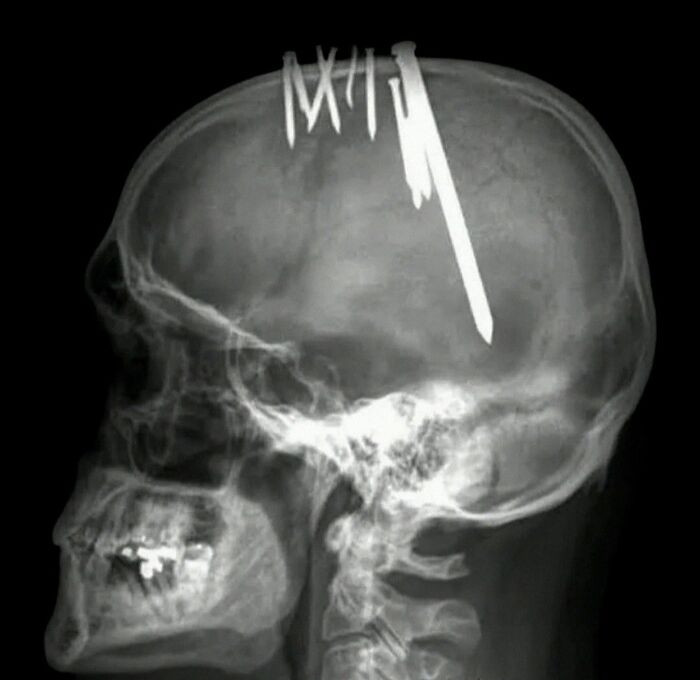

44-летний мужчина обратился в скорую, жалуясь на сильные головные боли. Рентгенография показала 11 гвоздей, проникающих в мозг пациента. Он рассказал, что забивал их себе в голову, чтобы избавиться от зла. Мужчине поставили диагноз параноидальная шизофрения